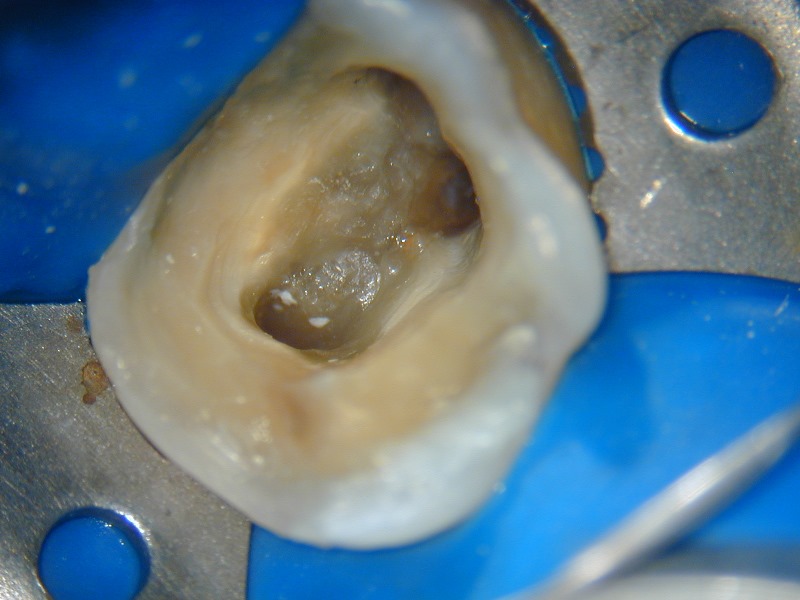

O microscópio operatório para odontologia foi desenvolvido para que pudéssemos ter a visibilidade necessária para detectarmos a entrada dos canais radiculares que recobertos por dentina ou por detritos nos impediam a completa descontaminação dos canais radiculares. Com ele também visualizamos e amplificamos a imagem para detectar possíveis trincas, fraturas ou calcificações que impedem o tratamento. Observem as fotos dos casos clínicos que mostram como conseguimos trabalhar e fotografar os casos com a máquina acoplada ao MO.

Localização com o MO e ampliação da entrada dos canais - 5 canais em molar superior